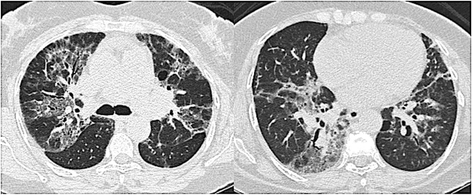

Results: There were 68 cases of ACIF, most of them women. The mean age was 57 ± 12 yr. Dyspnea, cough, restrictive pattern at spirometry and oxygen desaturation at exercise were common. A reticular pattern with peribronchovascular infiltrates was found in 79% of the cases. The etiologies of ACIF were hypersensitivity pneumonitis in 29 (42.6%), gastroesophageal reflux disease in 17 (25.0%), collagen vascular disease in 4 (5.9%), a combination of them in 15 cases and idiopathic in 3 (4.4%). The median survival was 116 months (95% CI = 58.5 - 173.5). Lower values of oxygen saturation at rest, presence of cough and some histological findings--organizing tissue in the airways, fibroblastic foci and microscopic honeycombing--were predictors of worse survival.